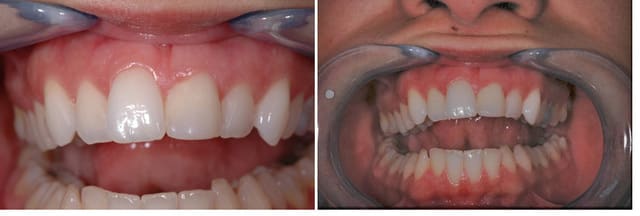

mais maintenant que j'ai publié l'avant, je me mets un point d'honneur de publier ce que j'en ferai.

donc première étape, ce sera la chir plastique, ensuite la facette.

et puis ensuite rendez-vous dans dix ans, même jour même heure...